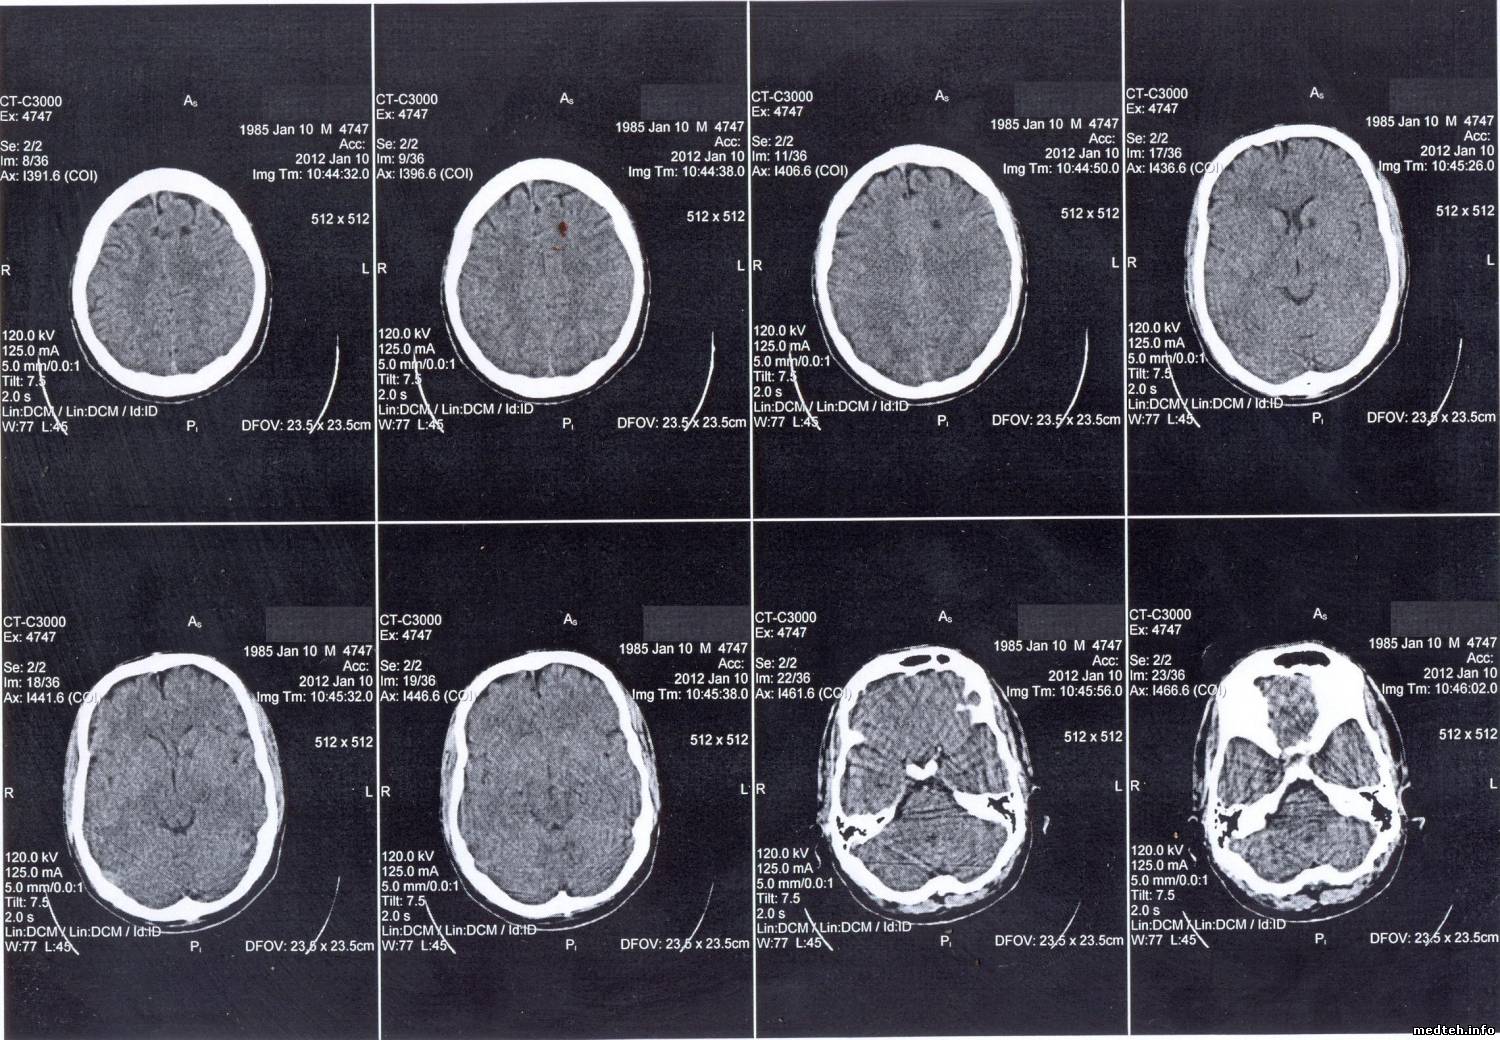

1. Черные точки в лобной доле правого полушария. Врачи говорят, что появляются внесистемно и они их путают с зоной ишемического инсульта. При повторных исследованиях головного мозга этого же пациента такой проблемы не обнаруживается. Говорят, что это связано с температурой. Как объяснить это, мне не очень понятно.

2. Хордообразные черные линии при снимках головного мозга. Появляются всегда в нижней части снимка, внесистемно. Что это такое, судить не берусь, было предположение, что это из-за проблемы с контактными кольцами в каком либо из положений возникает проблема с трубкой или с детекторами. (Кстати, на нижних снимках этой серии видны белые закорючки на месте ушей, это не сережки случаем? Хоть врачи и клялись, что такого быть не могло и это хрящи. Могут ли сережки чисто теоретически давать такие артефакты?)

3. Кольцевые круги. Врачи говорят, что зависит от температуры в помещении, где установлен томограф (там стоит мощная сплит-система), При 25 есть, при 21 градусе исчезает. По словам врачей, лечилось это раньше калибровкой по фантому. Пока ее не делал. Не совсем понимаю, как это связано с температурой.